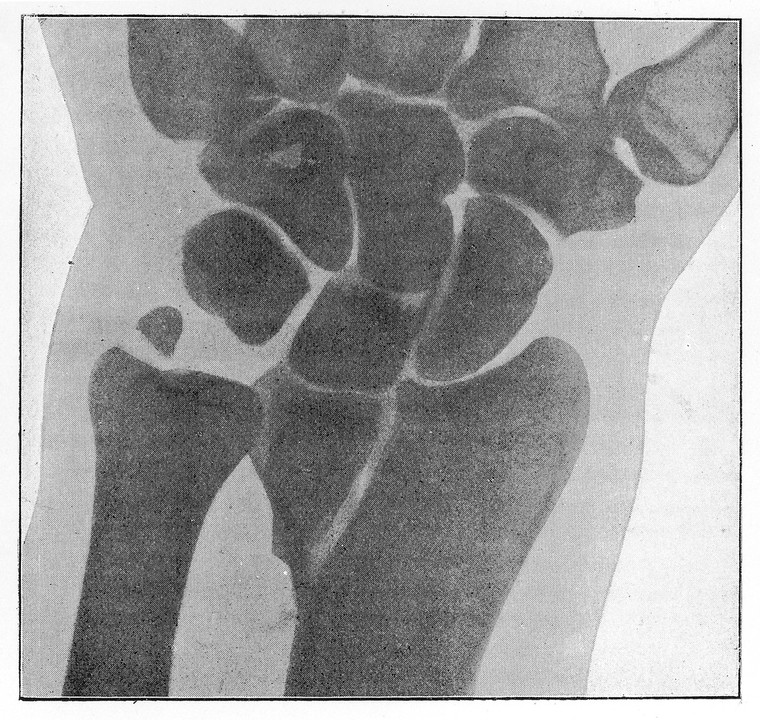

M0013197: Radiograph showing a double colles' fracture.

view M0013197: Radiograph showing a double colles' fracture.

M0013197: Radiograph showing a double colles' fracture. Public Domain Mark. Source: Wellcome Collection.

Photograph of a halftone reproduction of a radiograph showing a longitudinal fracture of the radius with slight impaction, and fracture of styloid process of ulna reproduced from Walsh, David: The Röntgen rays in medical work, London : Baillière, Tindall and Cox, 1897. Related images: M0013195, M0013196, M0013194, M0013198